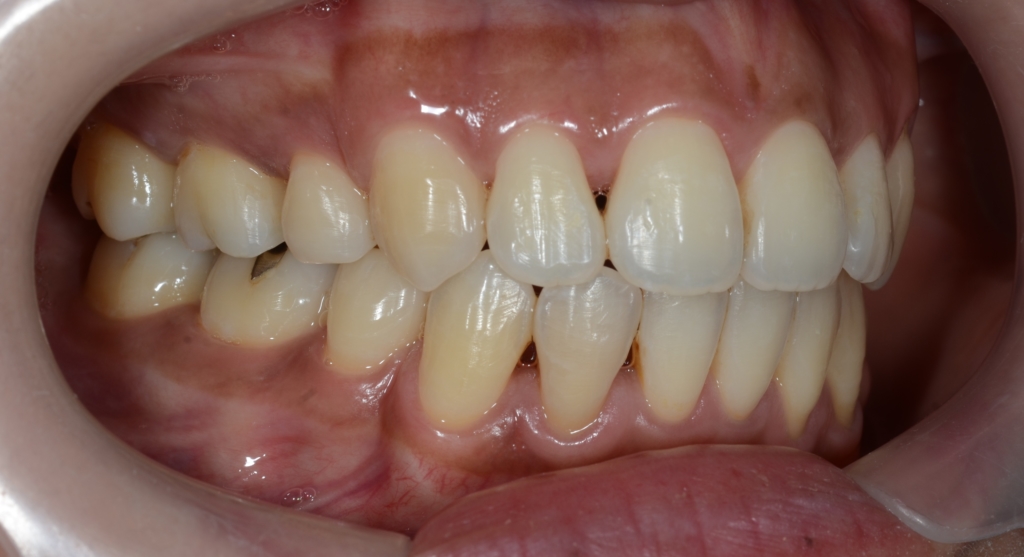

【Before】

#1.顎と歯の不調和による叢生(重度)

#2.上顎前突(奥歯の噛み合わせ)

と診断しました。

あらためて、矯正治療前後の歯並びと口元の変化を比べてみましょう。

まずは、歯並びの変化です。